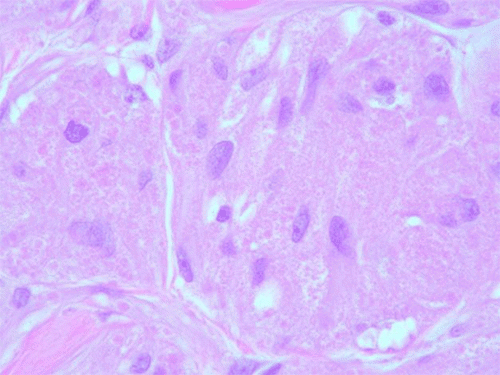

On colonoscopy, a solitary nodular lesion was found in the cecum with yellow discoloration, suggestive of a lipoma on gross examination (Figure 1). Gross appearance was lipomatous with a positive "pillow" sign. Biopsies were performed, and histology of the lesion revealed a granular cell tumor with IHC stains positive for S100, Calretinin, PAS, and CD68 and negative for AE1/3, CK7, CK20, Vimentin, and Desmin.

Figure 1. Solitary Submucosal Lesion in Cecum Seen on Colonoscopy. Published with Permission